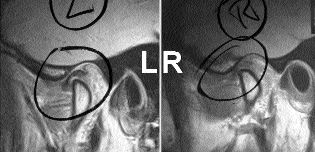

Diagnostic Imaging of the Temporomandibular Joint

Temporomandibular joint dysfunction (TMD) can affect a significant portion of the population.1 Clinical symptoms may include one or more of the following: pain in the region of the temporomandibular joint (TMJ), headaches, earaches, muscle tenderness, joint noises such as clicking, popping or grating, limited opening or deviation of the mandible on opening/closing, locking, and occlusal … Read more